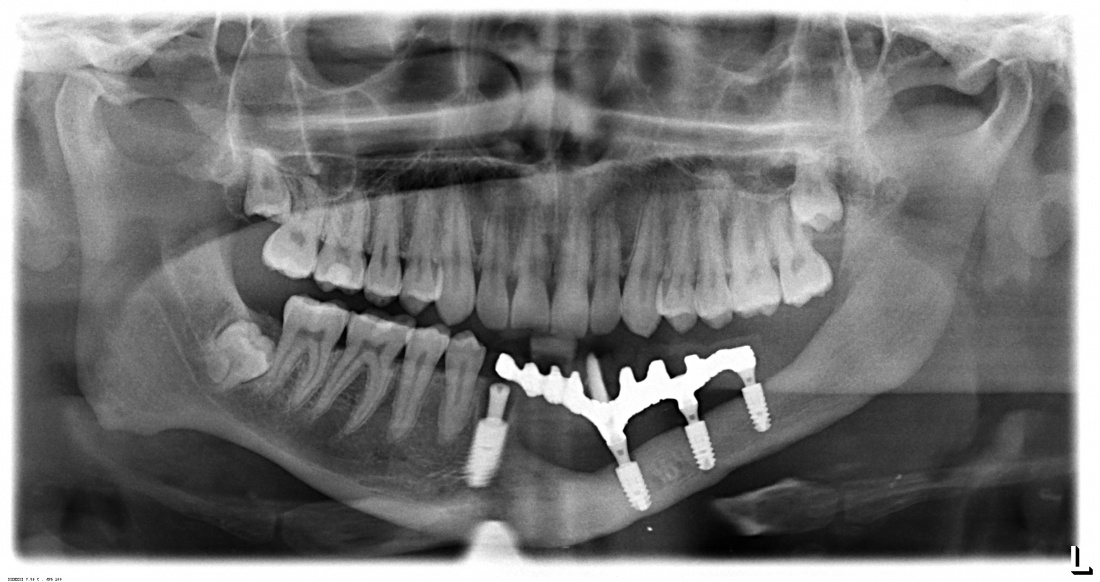

Итого, лечение Елены с первичного обращения до завершения постоянного протезирования заняло почти два года — 19 месяцев, если быть точным. Это как раз тот срок, на который нужно ориентироваться в подобных клинических случаях. В декабре 2019 года мы установили на имплантаты постоянные керамические коронки с винтовой фиксацией:

Несмотря на то, что Елена не испытывает никаких неудобств, жевательная функция полностью восстановлена, а состояние десны в области нижней челюсти слева совершенно нормальное, меня беспокоит состояние костной ткани в области имплантата 36 зуба (отмечен стрелкой на снимке). Я успокаиваю себя тем, что с момента установки формирователей десны здесь вообще ничего не изменилось, но всё же считаю, что перспективы у этого имплантата весьма мутные. Собственно, я предупредил об этом Елену, отметил важность хорошей гигиены полости рта и регулярных профилактических осмотров. В конце концов, наши гарантийные обязательства будут зависеть от того, насколько ответственно она отнесётся к моим рекомендациям.